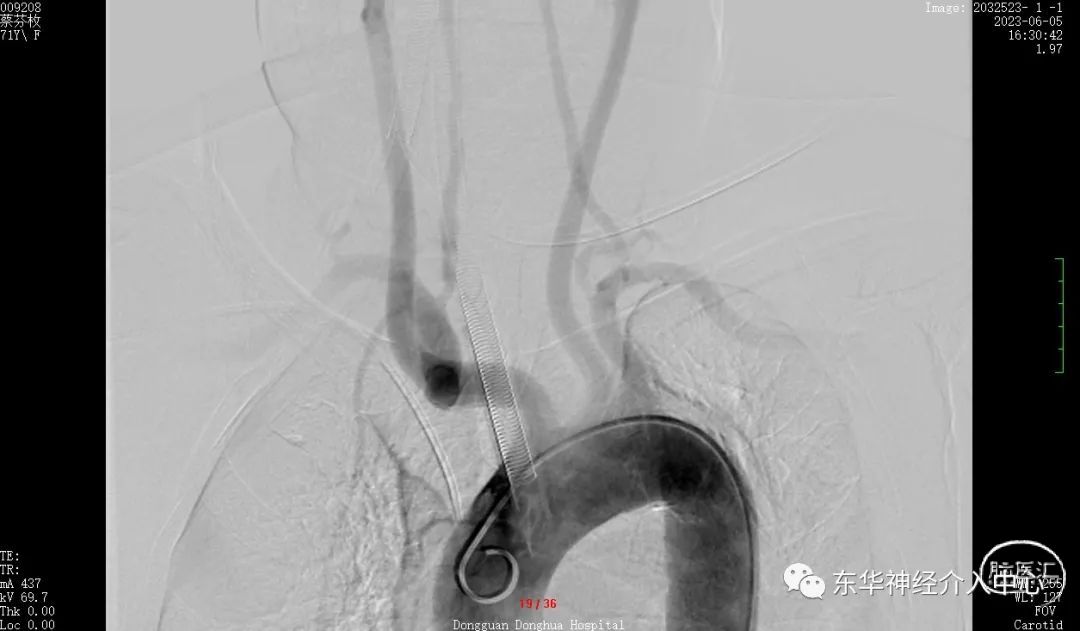

同侧椎动脉的开口狭窄,置入中间导管后血流不通畅。不得不进行开口的扩张。这倒是简单。扩张后顺利将中间导管置入合适位置。开始进行真正的动脉瘤栓塞术。

但是换用了三种微导丝都是难以将微导丝进入到PICA 的远端。考虑可能是动脉瘤稍远的PICA 内有斑块阻挡。微导丝不能到达远端,支架导管就不能进入其内,采取支架辅助栓塞动脉瘤已经不现实了。但是手术不可能放弃呀。曾经也拜读过有同道的文章采取微导丝来辅助栓塞动脉瘤、只能尝试一下了,但是风险更大、难度更高。不过令人欣慰的是经过反复的调整,第一个成篮圈非常满意。

可见载瘤动脉内微导丝与动脉瘤有间隙,说明动脉瘤成蓝非常满意。